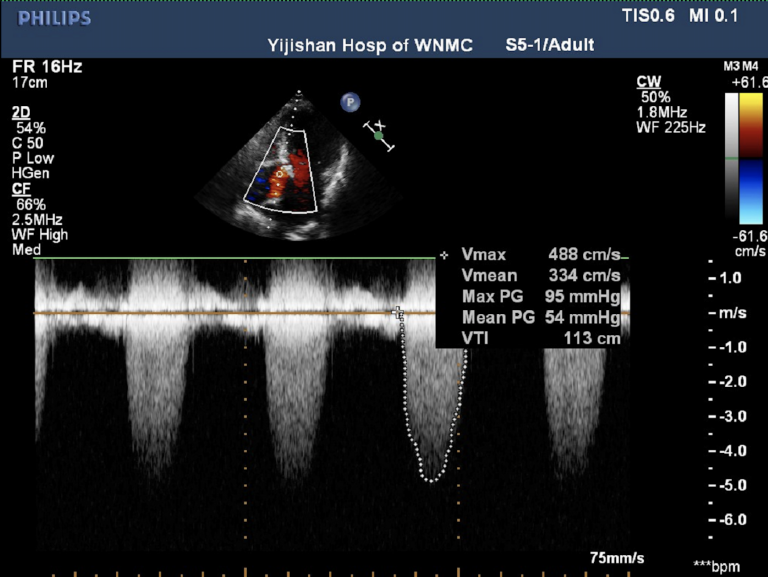

心脏超声

峰值流速4.88m/s,最高跨瓣压差95mmHg,平均跨瓣压差54mmHg,瓣口面积0.57cm²,左室射血分数EF 62%,左室舒张末期内径(LVD)44 mm。